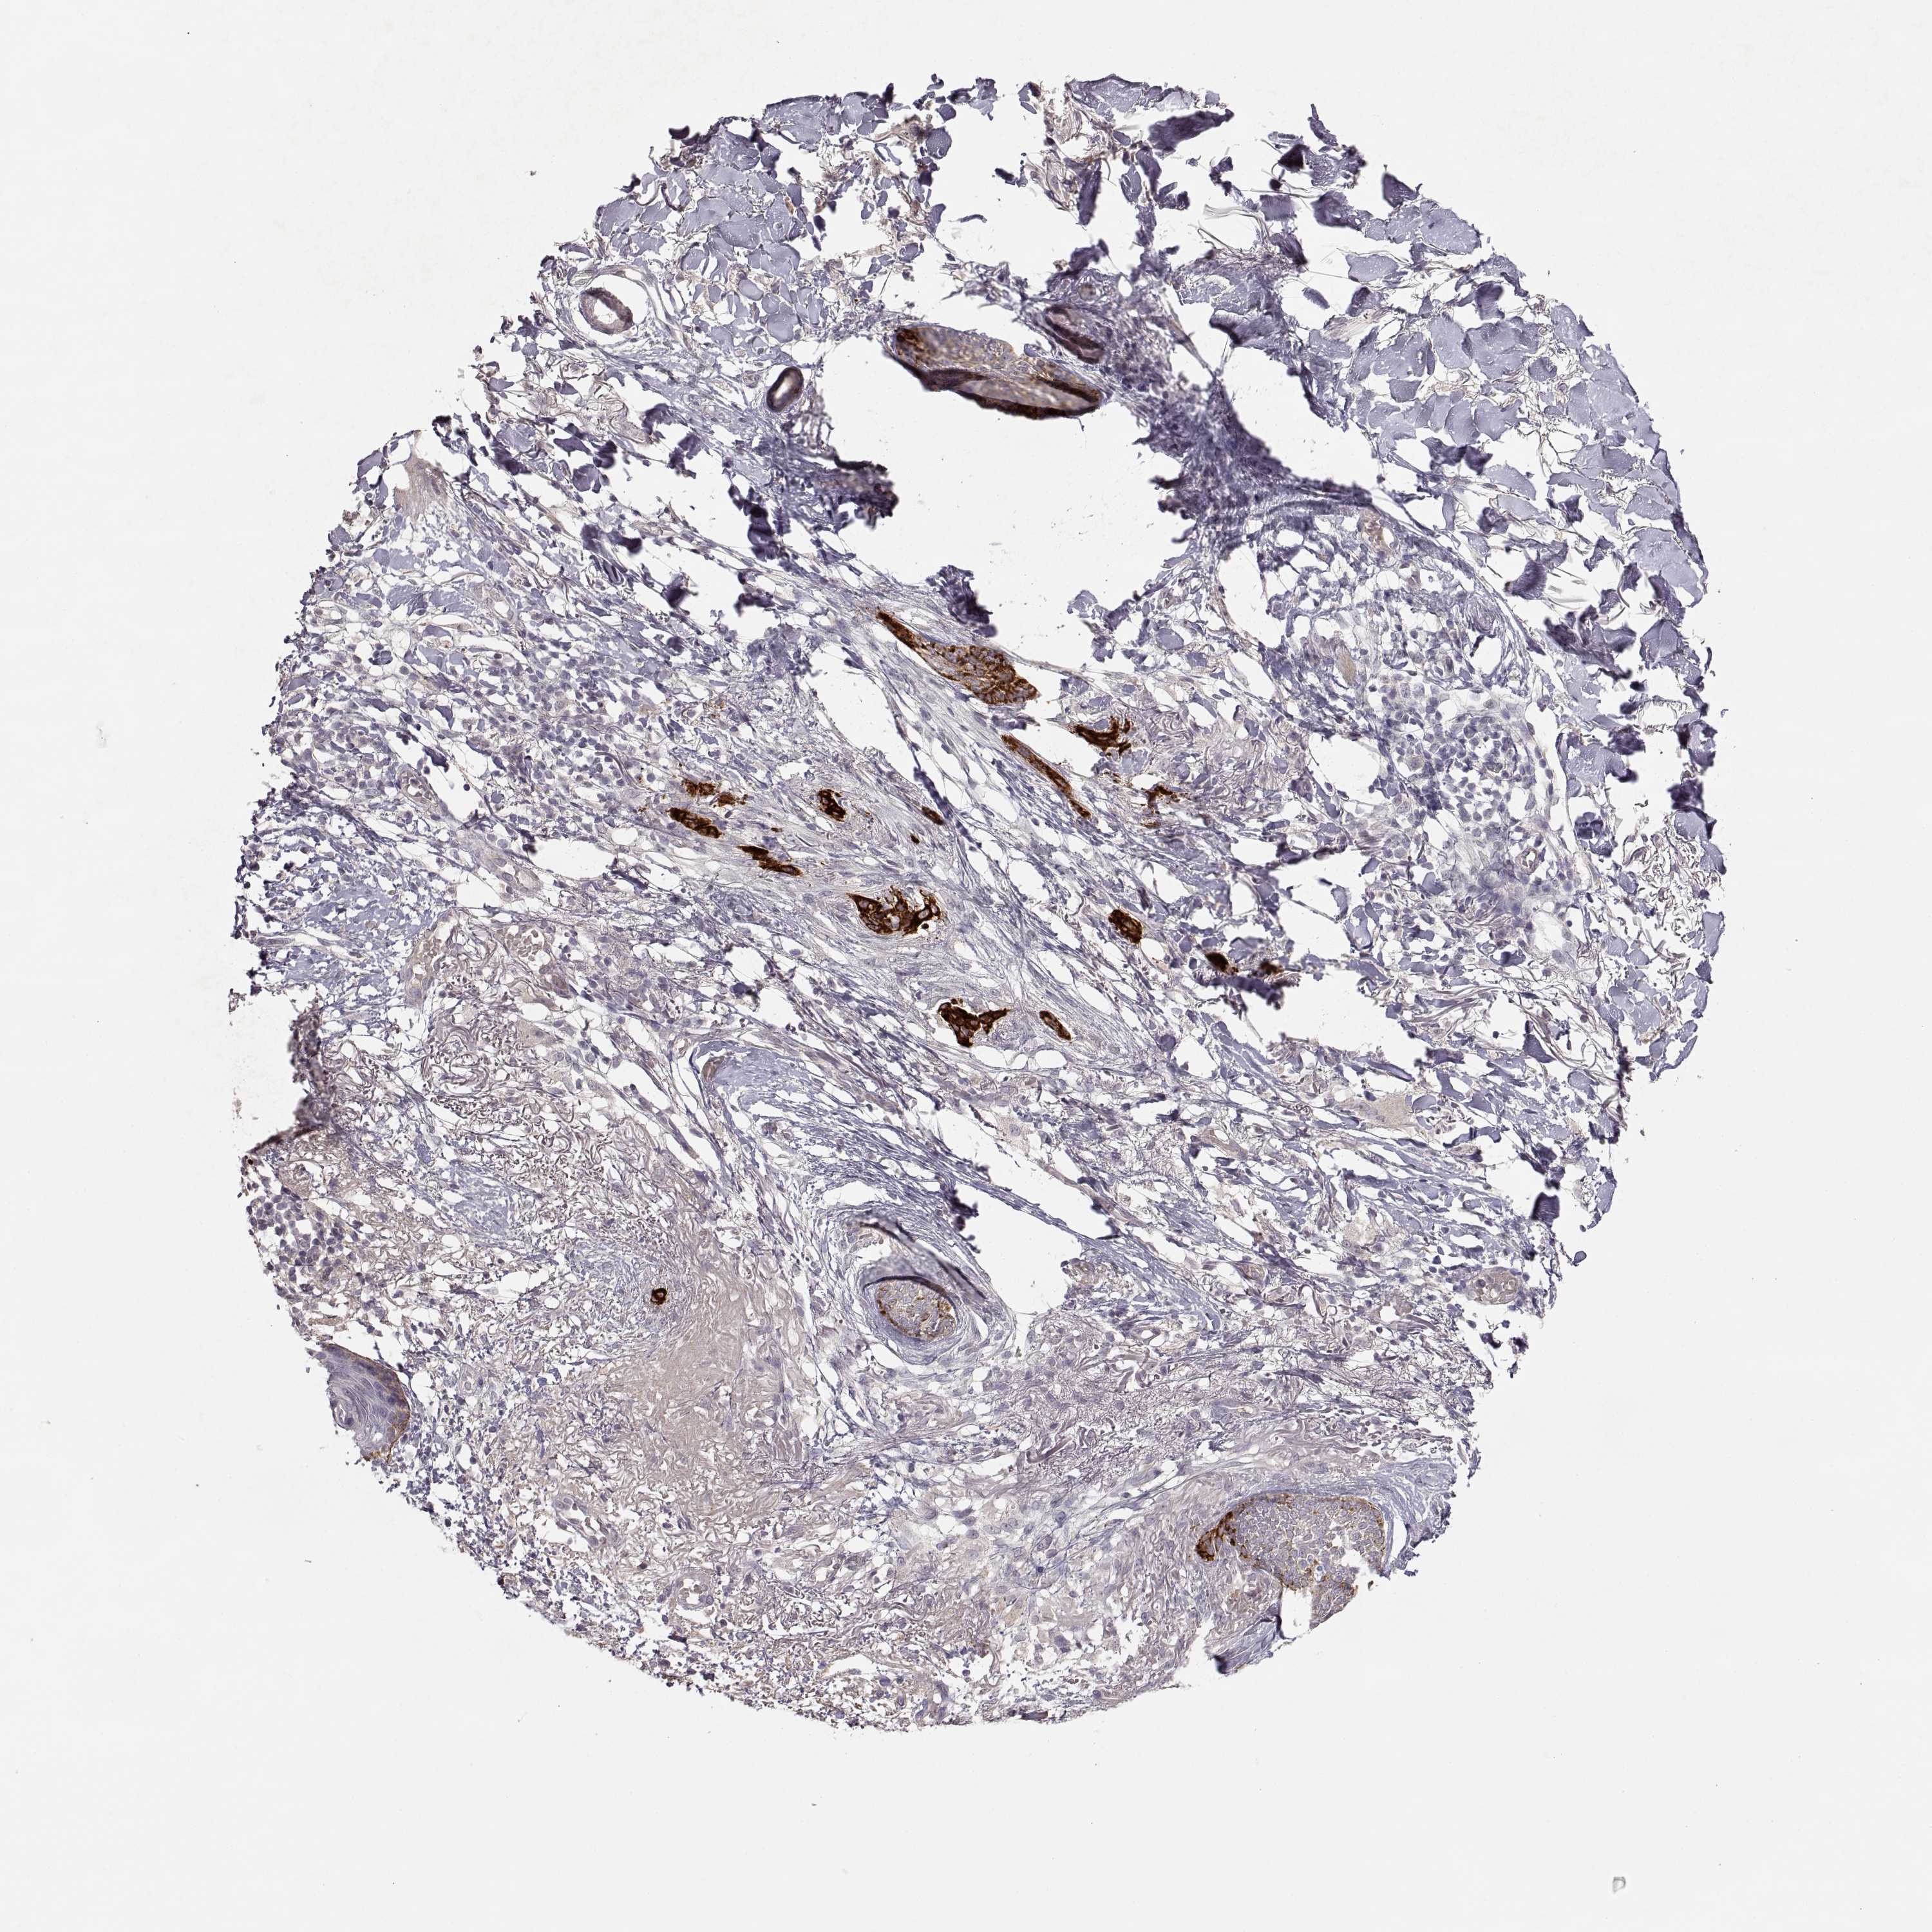

Basal cell and squamous cell cancer

SKIN CANCER - Protein expressioni

A mouse-over function shows sample information and annotation data. Click on an image to view it in a full screen mode. Samples can be filtered based on level of antibody staining by selecting one or several of the following categories: high, medium, low and not detected. The assay and annotation is described here.

Antibody stainingi

Antibody staining in the annotated cell types in the current human tissue is reported as not detected, low, medium, or high, based on conventional immunohistochemistry profiling in selected tissues. This score is based on the combination of the staining intensity and fraction of stained cells.

Each image is clickable and will lead to virtual microscopy that enables deeper exploration of all samples and also displays staining intensity scores, fraction scores and subcellular localization as well as patient and tissue information for each sample.

Antibody CAB004257

Antibody CAB078165

Basal cell carcinoma

Squamous cell carcinoma, NOS